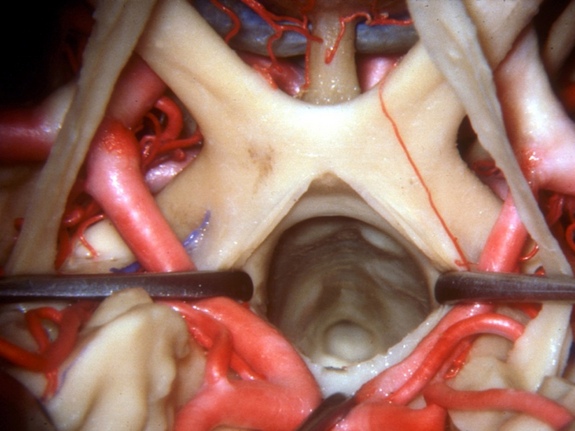

Mira hacia abajo en el quiasma óptico, un sitio que juega un papel importante en la vista. El quiasma óptico es la parte del cerebro donde se entrecruzan parcialmente las fibras axónicas de los nervios ópticos.